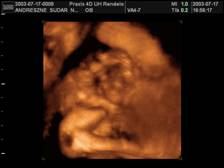

Arcocska